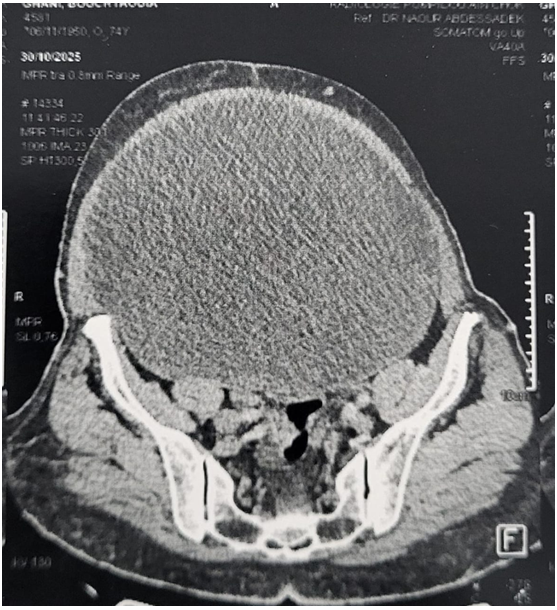

The abdominal-pelvic CT scan reveals a large cystic massin the abdomen and pelvis containing fluid, with a thin wall, partitioned, without vegetation orisolated solid components, measuring 32 × 26 × 18 cm, consistent with a benign adnexal tumour Figure 2.

Figure 2. CT scan image of the abdominal mass